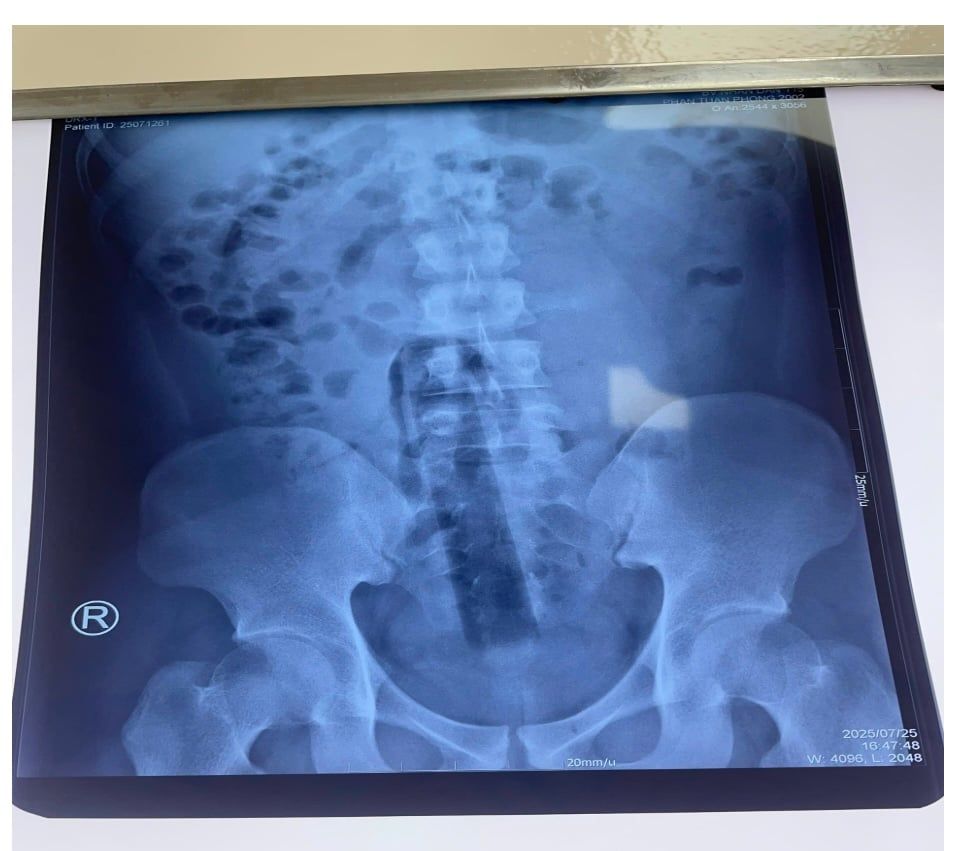

Người bệnh P.T.P. 23 tuổi, nhập viện trong tình trạng đau dữ dội vùng hậu môn, bí trung đại tiện, bụng chướng đau. Trước đó, người bệnh đã tự nhét một vật dài khoảng 15 cm vào hậu môn. Dị vật này không thể lấy ra được và đã trôi sâu vào trong trực tràng. Sau khi thăm khám và chụp X-quang, các bác sĩ xác định dị vật nằm sâu trong trực tràng và không thể lấy ra bằng phương pháp thông thường cũng như nội soi qua ngả hậu môn.

Hình 1. Hình ảnh dị vật trên phim X-quang bụng